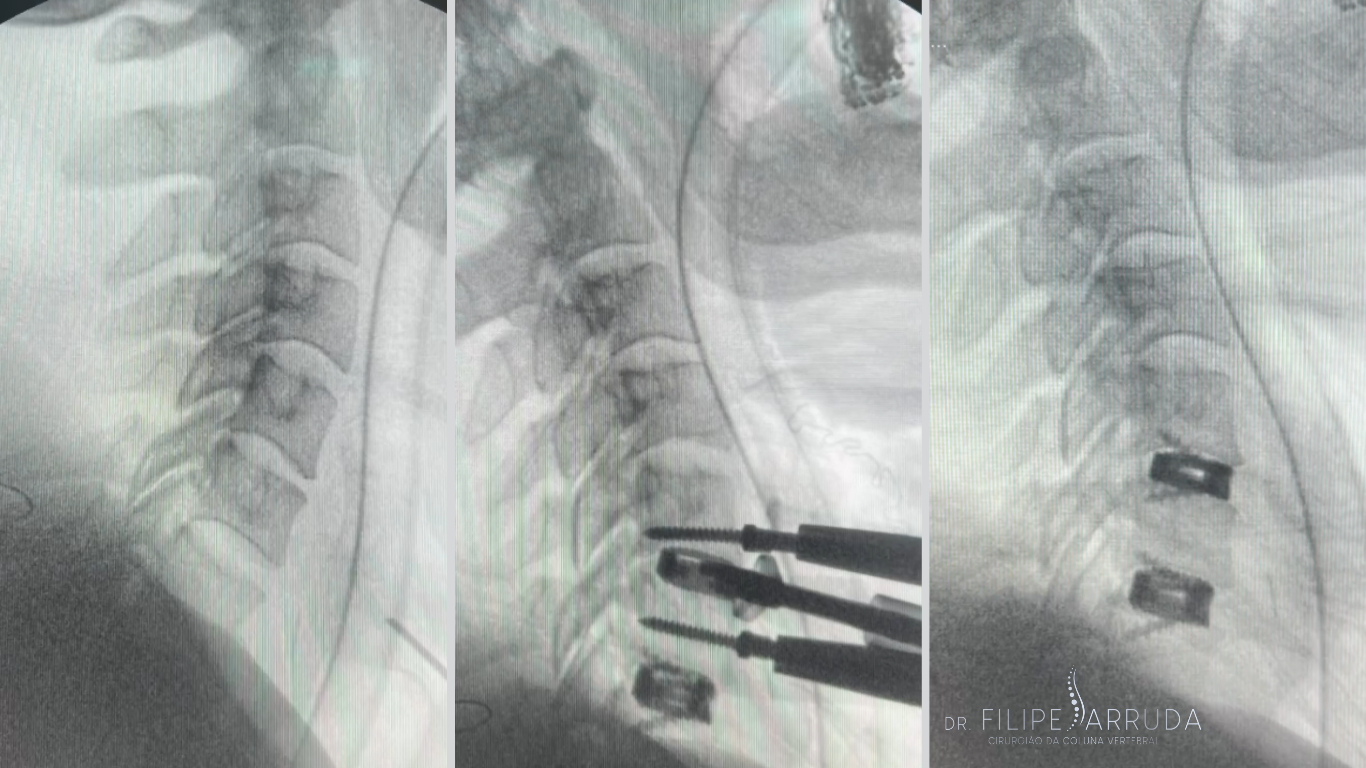

Procedimentos invasivos abertos: Restaurando a funcionalidade da coluna com precisão e implantes especiais para correção de deformidades e instabilidade.

Cuidando da coluna de forma menos invasiva: Técnicas modernas como a endoscopia de coluna oferecem incisões mínimas e recuperação mais rápida.